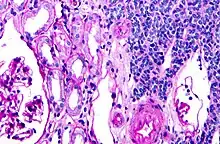

Micrograph of a metanephric adenoma with structures reminiscent of those seen in papillary renal cell carcinoma. H&E stain.

Metanephric adenoma (MA) is a rare, benign tumour of the kidney, that can have a microscopic appearance similar to a nephroblastoma (Wilms tumours),[1] or a papillary renal cell carcinoma.

Metanephric adenoma is diagnosed histologically. The tumours can be located at upper pole, lower pole and mid-hilar region of the kidney; they are well circumscribed but unencapsulated, tan pink, with possible cystic and hemorrhagic foci. They show a uniform architecture of closely packed acinar or tubular structures of mature and bland appearance with scanty interposed stroma.[3][4][5][6][7] Cells are small with dark staining nuclei and inconspicuous nucleoli. Blastema is absent whereas calcospherites may be present. Glomeruloid figures are a striking finding, reminiscent of early fetal metenephric tissue. The lumen of the acini may contain otherwise epithelial infoldings or fibrillary material but it is quite often empty. Mitoses are conspicuously absent.[3][4][5][6][7] In the series reported by Jones et al. tumour cells were reactive for Leu7 in 3 cases of 5, to vimentine in 4 of 6, to cytocheratin in 2 of 6, to epithelial membrane antigen in 1 of 6 cases and muscle specific antigen in 1 of 6.[5] Olgac et al. found that intense and diffuse immunoreactivity for alpha-methylacyl-CoA racemase (AMACR) is useful in differentiating renal cell carcinoma from MA but a panel including AMACR, CK7 and CD57 is better in this differential diagnosis.[8] Differential diagnosis may be quite difficult indeed as exemplified by the three malignancies initially diagnosed as MA that later metastasized, in the report by Pins et al.[9]